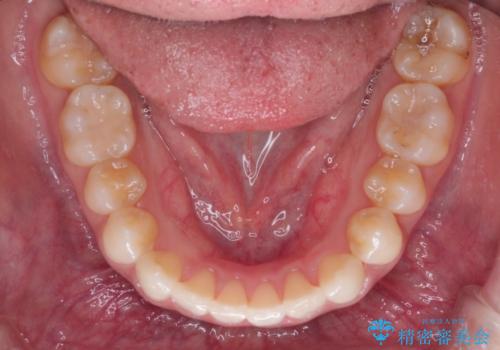

前歯のがたつきと反対咬合 インビザラインによる矯正治療

- 前歯のがたつきと反対咬合を主訴に来院されました。

下の前歯のがたつきを改善するために、右下の奥歯を後方に移動させるのと、歯と歯の間をわずかに削り、歯を並べる計画としました。

前歯の正中のずれを修正するのに少し時間がかかりましたが、整った歯並びにすることができました。